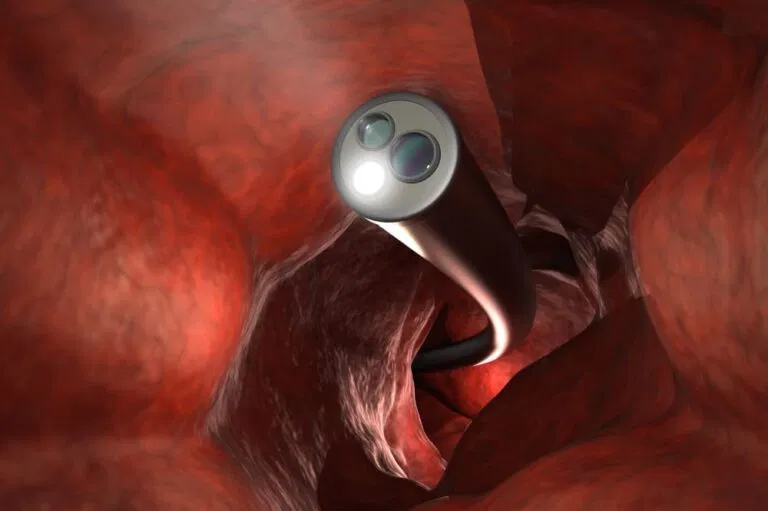

ما هي الاشعة التداخلية المستخدمة في علاج دوالي الخصية؟

تعتبر الاشعة التداخلية إحدى تخصصات العلوم الطبية، حيث يقوم استشاري الاشعة التداخلية بتشخيص الأمراض وعلاجها معا بالاستعانة بطرق تصوير الاشعة. كما يمكن علاج مجموعة واسعة من الأمراض وعلاج الأورام المختلفة عن طريق إدخال أدوات صغيرة مثل ال قسطرة أو الأسلاك من خارج الجسم. وتساعد تقنيات الأشعة السينية (X-Ray) والتصوير بالاشعة المقطعية (CT) و الموجات فوق الصوتية (US) (السونار) في توجيه هؤلاء الأطباء بدلاً من الجراحة التقليدية، وفي الكثير من الحالات تُغني الاشعة التداخلية عن دخول المستشفيات لاكثر من يوم.